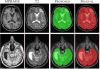

DEMON (DEep Multi-cONtrast skullstripping) is a deep convolutional neural network (CNN) based software tool to generate brainmasks (or skullstrip) from multi-contrast MR brain images, such as T1, T2, PD, or FLAIR. Unlike most other skullstripping methods, DEMON can take multi-contrast inputs, and based on multiple atlases, it generates a brainmask of a given subject image. It is especially useful for images with pathology such as traumatic brain injury (TBI), where most of the traditional skullstripping algorithms perform poorly. DEMON has been shown to be robust on both normal and pathological human brains, as well as rodent (mice and rats) brains.